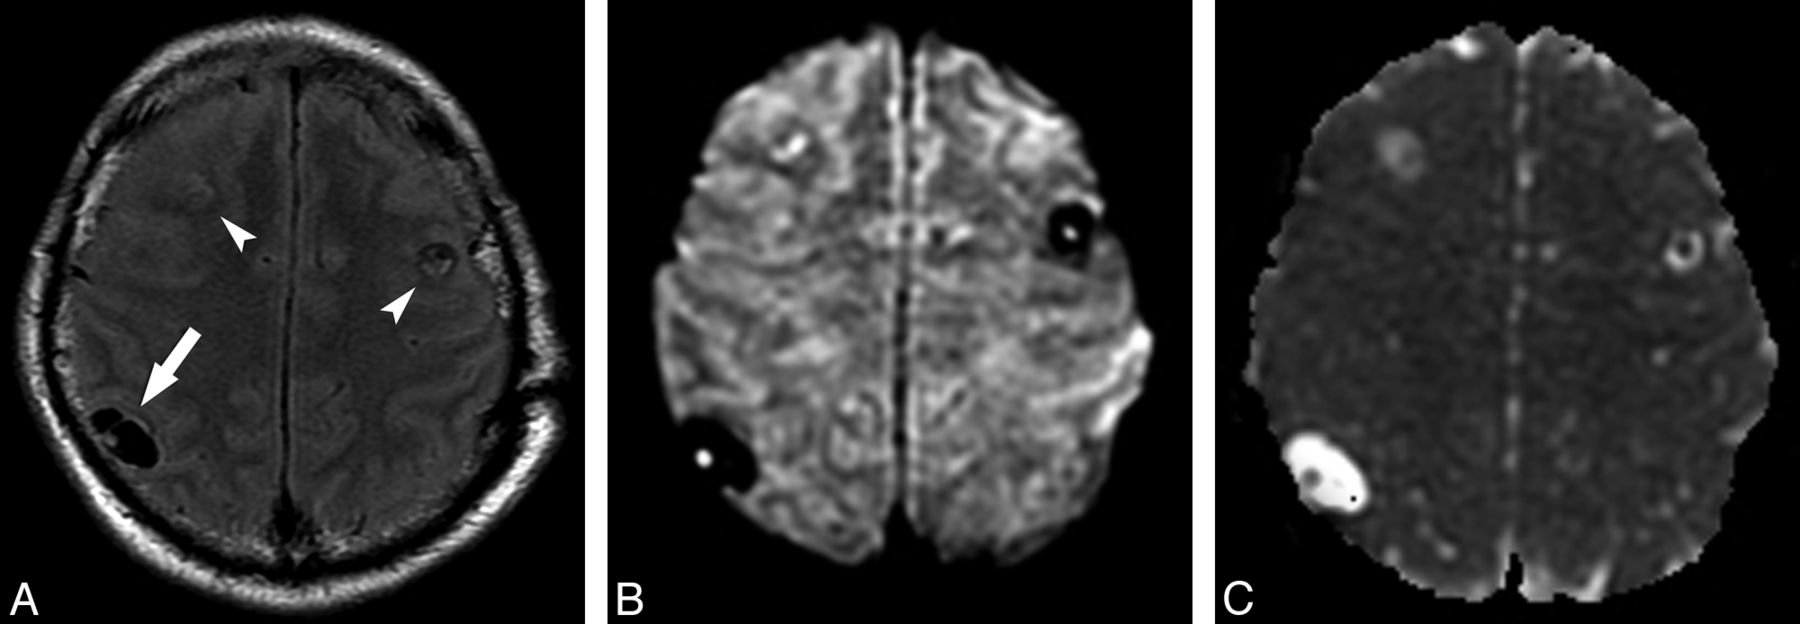

Fourteen of 65 lesions in the subarachnoid space (21.53%) had the small DWI hyperintensity suggestive of the scolex and iso-/hypointensity on ADC maps (Fig 4). In 2 of these subarachnoid lesions (16.66%), complete DWI hyperintensity was detected with low signal on the corresponding ADC maps, confirming the presence of reduced diffusion (Fig 5 and Table 2). Two of 14 intraventricular lesions (14.28%) also showed the DWI hyperintensity presumably corresponding to the scolex and iso-/hypointensity on ADC maps (Fig 6).

A small subarachnoid NCC lesion whose scolex is depicted only in DWI. Axial FLAIR (A) image demonstrates a hyperintense lesion in the right lateral temporal region (arrow). The DWI image (B) shows the curvilinear scolex in a transverse section as 2 hyperintense contiguous dots (arrow). Other lesions can be appreciated in the right thalamus. ADC map (C) discloses the scolex as iso-/hypointense dots.

Axial FLAIR sequence (A) in patient F demonstrates many subarachnoid cystic lesions in the right Sylvian cistern, compatible with the racemose form of NCC. Note specifically 1 lesion (arrows) that has signal intensity distinct from CSF. Axial DWI (B) image demonstrates homogeneous reduced diffusion in this small lesion (rADC = 0.79).

The intraventricular DWI hyperintense scolex is appreciated inside a lesion in the left lateral ventricle. The lesion and its scolex are well seen on the corresponding FLAIR image (A), but the scolex (arrow) is identified as a hyperintense dot in the DWI sequence (B). Additionally, other intraparenchymal NCC lesions are identified bilaterally.

Most interesting, though in a minority of cases, the eccentric dot or comma-shaped DWI hyperintensity allowed a more precise identification of the scolex compared with other sequences, including FLAIR. This phenomenon was noticed in 21 lesions in the vesicular stage (15.10%), 13 lesions in the colloidal vesicular stage (13.97%), and 7 (10.76%) in the subarachnoid space (Fig 4).